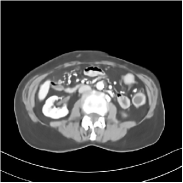

Fig. 3 illustrates the image evolution over SUPER layers (i.e., with evolving network weights in the iterative reconstruction process) for one test case, when using SUPER-WRN-ULTRA. It is apparent that in the early SUPER layers, the proposed SUPER-WRN-ULTRA method mainly removes noise and artifacts, while later SUPER layers mainly reconstruct details such as the bone structures shown in the zoom-in box. A similar behaviour is observed with FBPConvNet-based SUPER methods, which are shown in the supplement (Figs. 13 and 14).

Refer to caption Refer to caption Layer 1RMSE =27.44 HURefer to caption Refer to caption Layer 5RMSE = 26.03 HU

Refer to caption Refer to caption Layer 11RMSE = 25.91HURefer to caption Refer to caption Reference

Figure 3: Image evolution over SUPER layers using the SUPER-WRN-ULTRA method. RMSE values are also indicated.